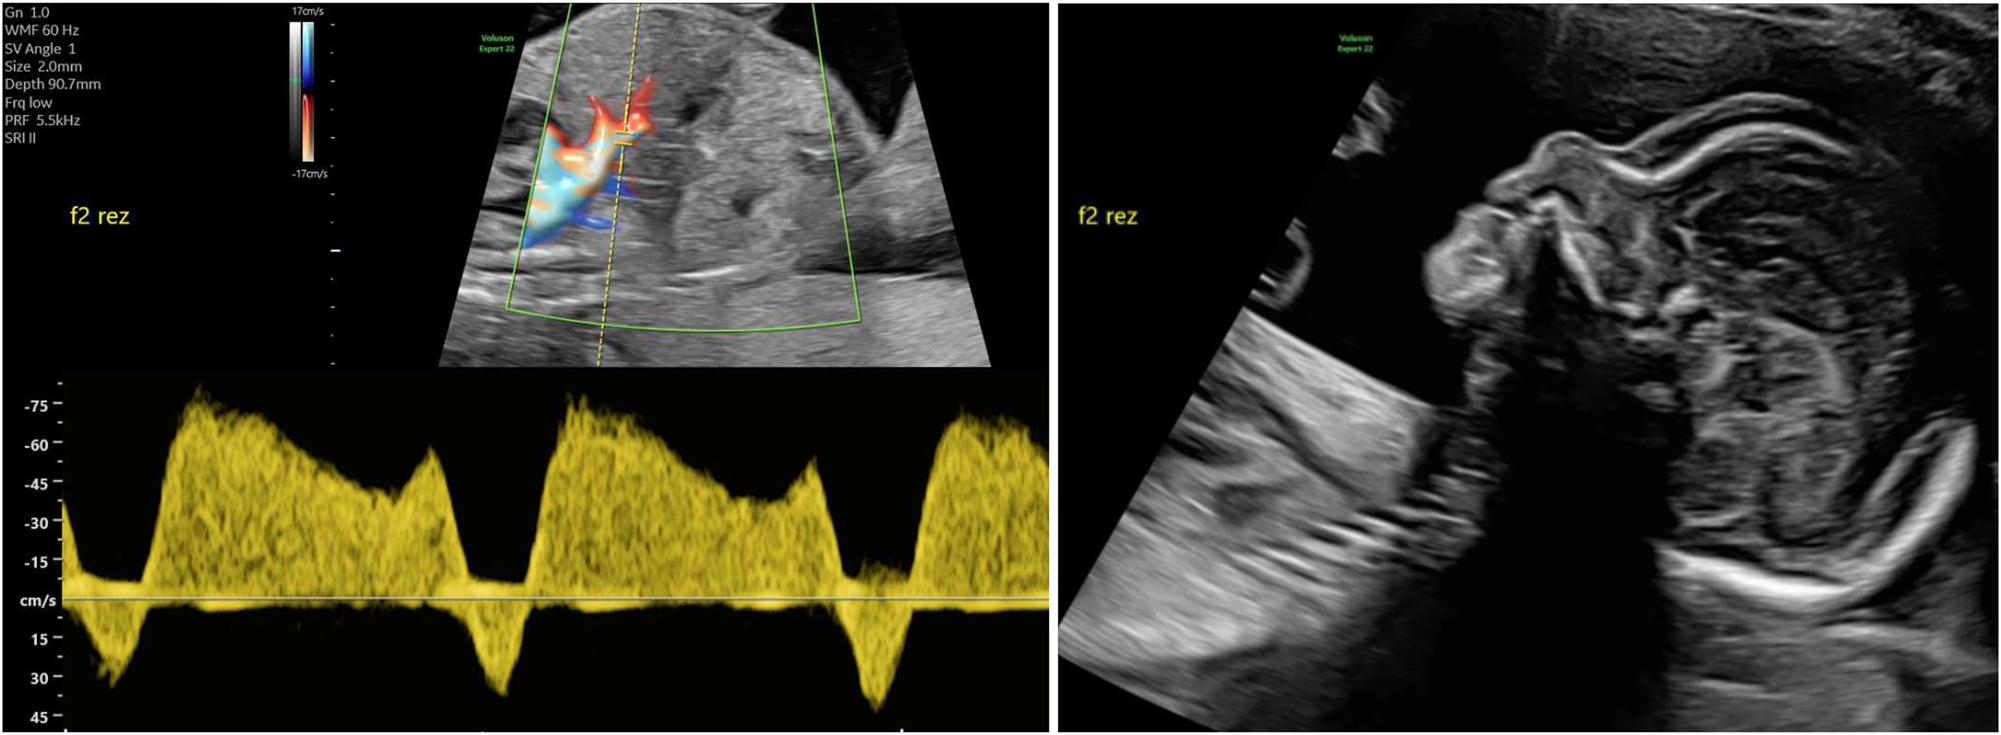

A rare variant of interfetal transfusion in monochorionic twins is twin reversed arterial perfusion (TRAP) sequence, which occurs in approximately 2.5 % of monozygotic twins [7], 8]. This involves reversed perfusion of the commonly singular umbilical artery of the affected twin via a large-caliber arterio-arterial anastomosis, resulting in disrupted development of the heart and the upper body (Figure 6). While the affected fetus has no chance of survival, the healthy pump twin is also at risk due to excessive strain on the heart [65].

Sonographic image of a rudimentary TRAP fetus (22 + 4 weeks of gestation) with typical reversed arterial perfusion in the singular umbilical artery.

Diagnosis can be made by demonstrating reversed perfusion in the umbilical artery of the TRAP fetus using Doppler sonography. Monitoring the ductus venosus of the pump twin can be used to detect cardiac decompensation in a timely manner.